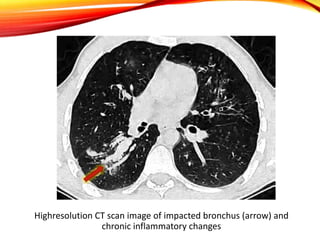

Radiological findings

• Typical findings are parenchymal infiltrates

and bronchiectasis

• They have a predilection for upper lobes

• “finger-in-glove opacities”

• “tramline shadows”

• “toothpaste shadows”

• “ring shadows”

• lobar consolidation

Extensive infiltrates with tubular configuration

and ‘‘gloved finger” appearance

Highresolution CT scan image of impacted bronchus (arrow) and

chronic inflammatory changes